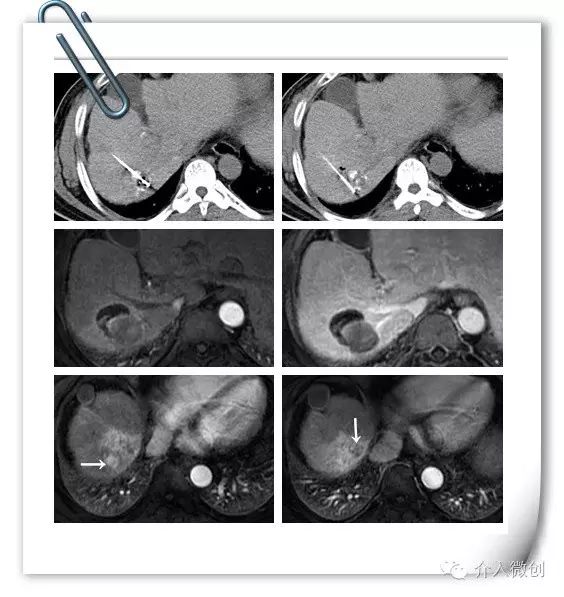

针对病灶碘油沉积欠缺情况,予以行CT引导下射频消融,治疗后病灶中心出现气化。

射频消融治疗

射频消融后1个月复查MRI提示病灶完全消融,边缘可见胆汁瘤,患者无发热、黄疸等不适。但近膈顶部可见2个小结节新发病灶,甲胎蛋白(AFP:244ug/ml)亦未明显下降。